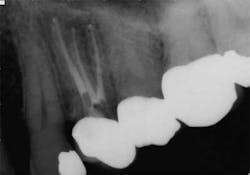

While mandibular incisors are my least favorite teeth to treat, the premolar teeth also provide significant reason for concern as they have highly variable anatomy. The maxillary first and second premolars will have one, two, or three roots and canals. (Figure 3) Maxillary premolar teeth have the smallest mean apical dimension at the apex (11) and the most variable anatomy, with exception of third molars. (12,17) The roots are often very thin, and a bulbous clinical crown may have significant taper to a thin root in the mesial-distal dimension that is broad in the facial-lingual dimension. It is not uncommon to see mesial-distal fractures in maxillary first or second premolars. Maxillary second premolars may have more curvature in the apical portion of the root when the sinus is close to the root ends. (Figure 4)

following root canal treatment in teeth Nos. 4 and 5. An angled

radiograph indicated a high probability for an untreated canal in

tooth No. 4 and as a result, this tooth was retreated.

increased concern about the anatomy in tooth No. 5. This tooth

was subsequently retreated due to persistent symptoms.

were present in both Nos. 4 and 5 following the initial root

canal treatment.